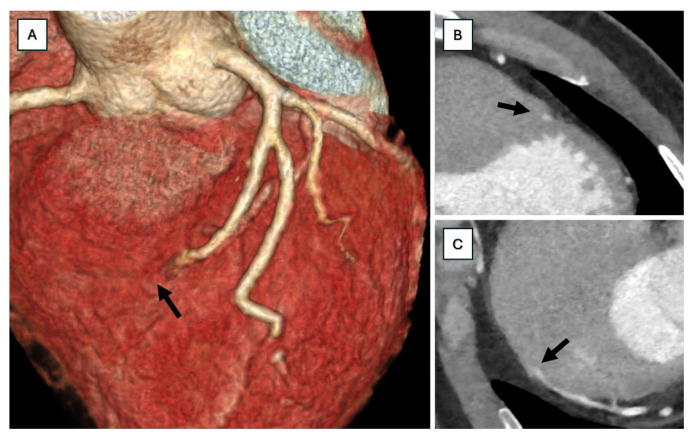

心肌桥(MB)是一种先天性冠状动脉异常,其中一段冠状动脉在心内运行。我们提出的情况下,38岁的男性心肌桥左前降支谁发展运动性心绞痛。本病例强调了在心绞痛患者的诊断检查中,尤其是在年轻人中,认识到MB作为缺血原因的重要性,这一点不应被忽视。一个全面的诊断方法,包括多模态成像,是必要的,以揭示病理。建议采用量身定制的药理学策略。长期临床随访是优化症状管理和减少并发症的关键。

Myocardial bridging (MB) is a congenital coronary anomaly in which a segment of a coronary artery runs intramyocardially. We present the case of a 38-year-old male with myocardial bridging in the mid-left anterior descending artery who developed exercise-induced angina. This case underscores the importance of recognizing MB as a cause of ischemia that should not be overlooked in the diagnostic workup of patients with angina, especially in younger individuals. A comprehensive diagnostic approach, including multimodality imaging, is essential to uncover the pathology. A tailored pharmacological strategy is recommended. Long-term clinical follow-up is crucial for optimizing symptom management and reducing complications.